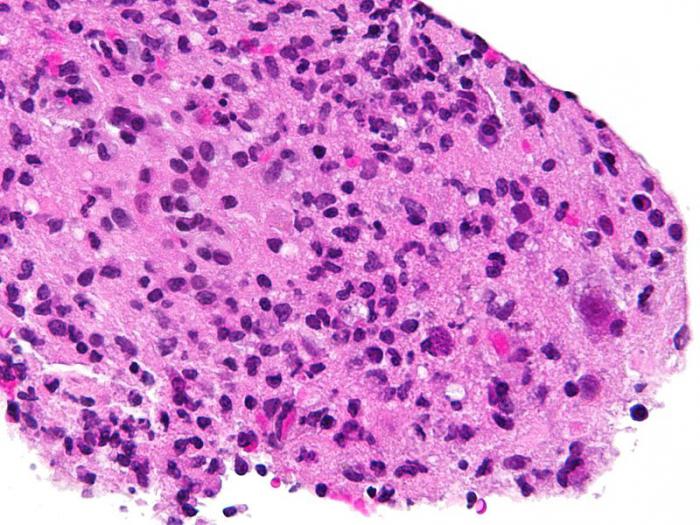

Что же за зверь такой – токсоплазма? Это простейшие внутриклеточные паразиты, напоминающие под микроскопом дольки апельсина. Цисты – мешочки с токсоплазмами — попадают в почву через фекалии заболевших кошек, и уже оттуда с водой, землей, ветром, с пылью на обуви и колесах автомобилей распространяются дальше. С загрязненным землей кормом эти цисты попадают в организм других животных – собак, мышей, крыс, а также сельскохозяйственных, мясо которых затем идет в пищу.

Признаки токсоплазмоза: блокаторы иммунитета

Токсоплазма — одноклеточный организм, похожий под микроскопом на каплю или дольку мандарина. Попав в организм, он сначала оказывается в нижних отделах тонкого кишечника, где проникает в клетки эпителия, то есть тканей, покрывающих кишку изнутри. Затем он начинает путешествовать с кровью или лимфой и оседает в лимфатических узлах, где обоснуется внутри клеток иммунной системы — макрофагов. Макрофаги, заселенные токсоплазмами, не могут выполнять свои защитные функции. Они становятся просто хранилищем возбудителя и вскоре погибают. Можно даже сказать, что токсоплазмы блокируют иммунитет.